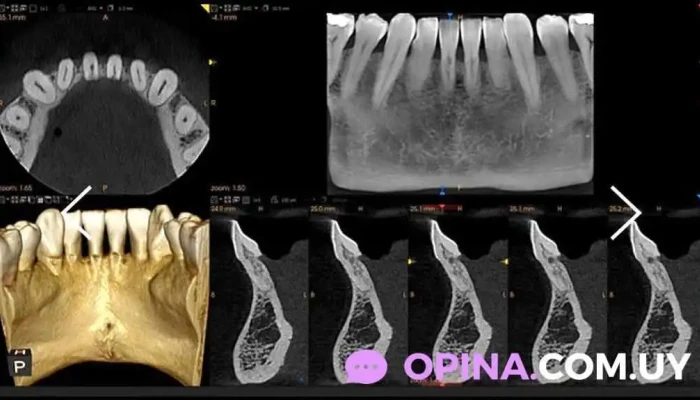

La radiología permite a los odontólogos obtener imágenes precisas de la estructura dental y de los tejidos circundantes. Esto es esencial para identificar problemas como caries, infecciones y enfermedades periodontales, así como para planificar tratamientos más complejos.

En la Cio Clínica de Imagen, se ofrecen diversos servicios relacionados con la radiología odontológica, tales como:

- Radiografías periapicales

- Radiografías panorámicas

- Tomografías computarizadas

El Dr. Gabriel Ruiz Figares cuenta con tecnología de última generación que garantiza la calidad y seguridad de las imágenes obtenidas. Esto permite realizar diagnósticos más acertados y eficaces.